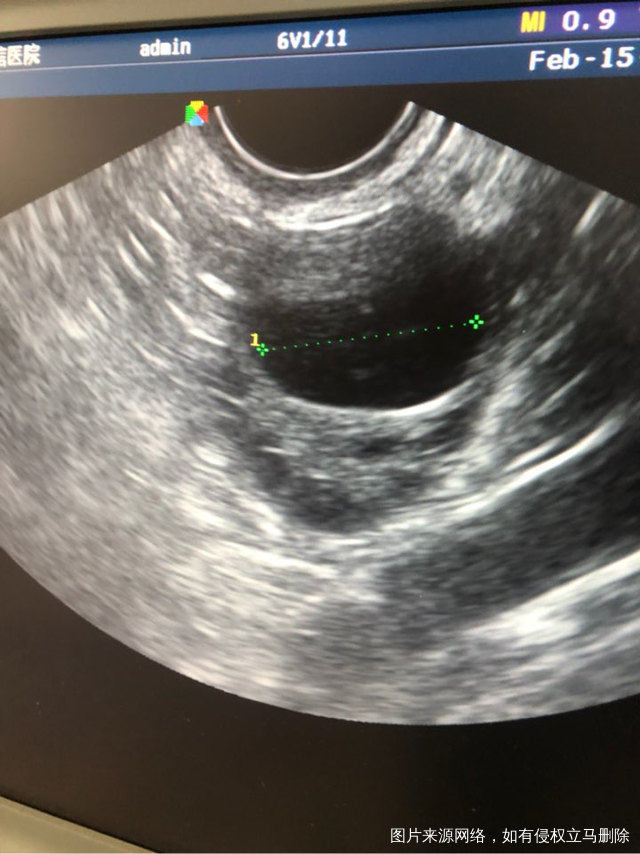

今天周期第21天,内膜0.75卵泡2.3×1.5